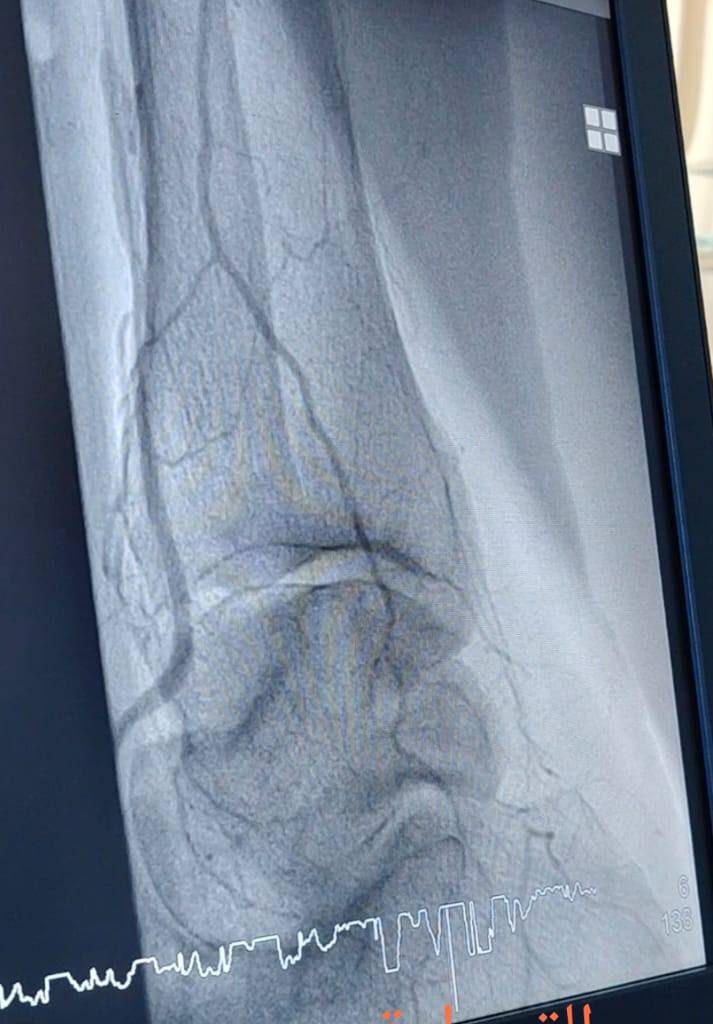

“استقبلنا حالتين لمريض ومريضة في السبعينات من العمر، كانا يعانيان من انسداد كامل في شرايين الساقين نتيجة تصلب الشرايين، مع وجود قدم سكري وبداية حدوث كانكرين؛ إحداهما في الساق الأيسر والأخرى في الساق الأيمن.”

“تم إجراء عمليتين للقسطرة الشريانية، حيث عملنا على فتح الانسدادات في الشرايين الطرفية وعلاج قصور الشرايين، ما ساهم في إعادة جريان الدم إلى الساقين والقدمين بعد أن كانت الحالتان مهددتين بالبتر.”

“الحمد لله، تكللت العمليتان بالنجاح، وتم استعادة التروية الدموية بشكل جيد، الأمر الذي ساعد على إنقاذ الساقين من البتر.”